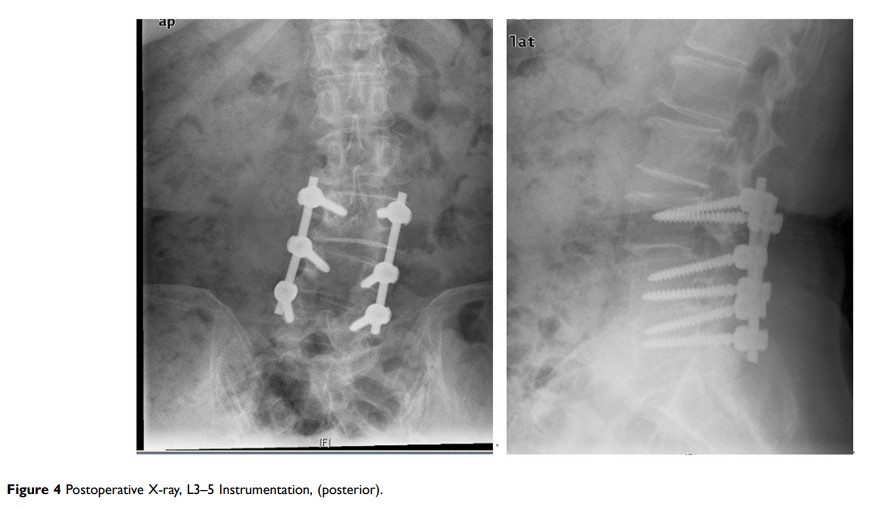

脊柱硬膜外脓肿 11 例与文献回顾